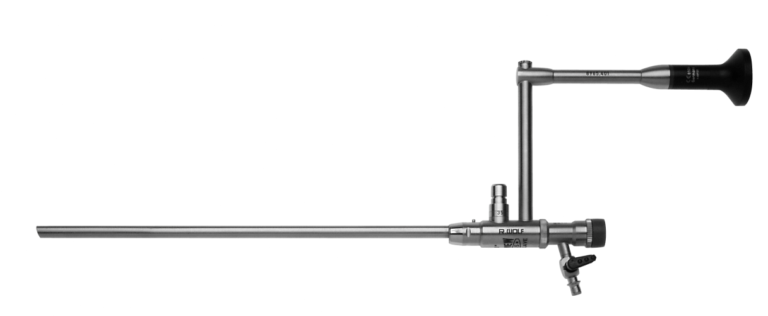

Uretrotomía Interna

Vaina de Uretrónomo Obturador

Vaina de uretrotomo de 21 Fr.

Elemento de Trabajo

Bisturí Recto

Bisturí Redondo

Equipo de Cistoscopía

Lente de 30°

Puente corto